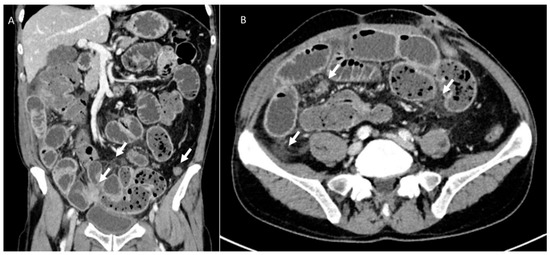

3.4. Urological Injury

- Halabi, W.J.; Jafari, M.D.; Nguyen, V.Q.; Carmichael, J.C.; Mills, S.; Pigazzi, A.; Stamos, M.J. Ureteral injuries in colorectal surgery: An analysis of trends, outcomes, and risk factors over a 10-year period in the United States. Dis. Colon Rectum 2014, 57, 179–186. [Google Scholar] [CrossRef]

- Esparaz, A.M.; Pearl, J.A.; Herts, B.R.; LeBlanc, J.; Kapoor, B. Iatrogenic urinary tract injuries: Etiology, diagnosis, and management. Semin. Interv. Radiol. 2015, 32, 195–208. [Google Scholar] [CrossRef]

- Potenta, S.E.; D’Agostino, R.; Sternberg, K.M.; Tatsumi, K.; Perusse, K. CT Urography for Evaluation of the Ureter. Radiographics 2015, 35, 709–726. [Google Scholar] [CrossRef]